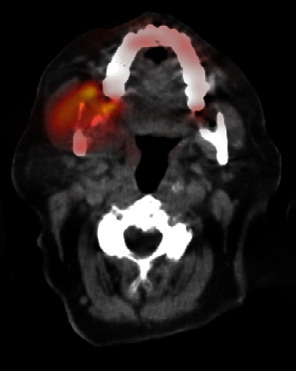

Primary mandibular telangiectatic osteosarcomas are very rare lesions, with only nine cases reported. Histologically, these lesions show multiple cystic blood-filled cavities traversed by neoplastic bone in septa lined by high-grade malignant cells. Here, we report an 81-year-old woman who presented with a mandibular mass, which was surgically resected and analyzed by histologic examination and whole exome DNA sequencing. A diagnosis of telangiectatic osteosarcoma was given. Comparative sequencing data analysis of paired benign and tumor DNA revealed 1577 variants unique to the tumor DNA, which clustered into several gene families, including those regulating DNA repair and apoptosis. Comparison of benign and tumor DNA revealed many shared gene polymorphisms associated with an increased cancer risk. These included polymorphisms in the ATM, p53, BRCA1, and BRCA2 and many other genes. Interestingly, the patient's family history showed an unusually high cancer incidence, likely related to these cancer risk-associated polymorphisms. To our knowledge, this is the first-time sequencing applied to a mandibular telangiectatic osteosarcoma. Our findings may shed light on the molecular origins of these rare tumors and how they may relate to other tumors in related kindreds.